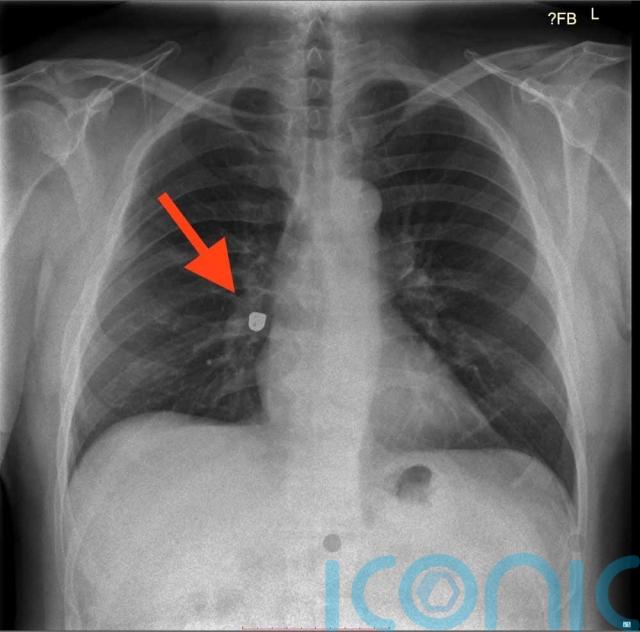

Paul knew that something was amiss and after his appointment he rushed to A&E, and was horrified when an X-ray revealed his gold crown had become lodged in his right lung and the grandad of two needed emergency surgery.

Thankfully, Paul was able to get his much-needed X-ray but was horrified when medics revealed his gold crown was lodged in his right lung.

“It was restricting 60 per cent of the air flow. I was told the only way to get it out was under general anaesthetic.”